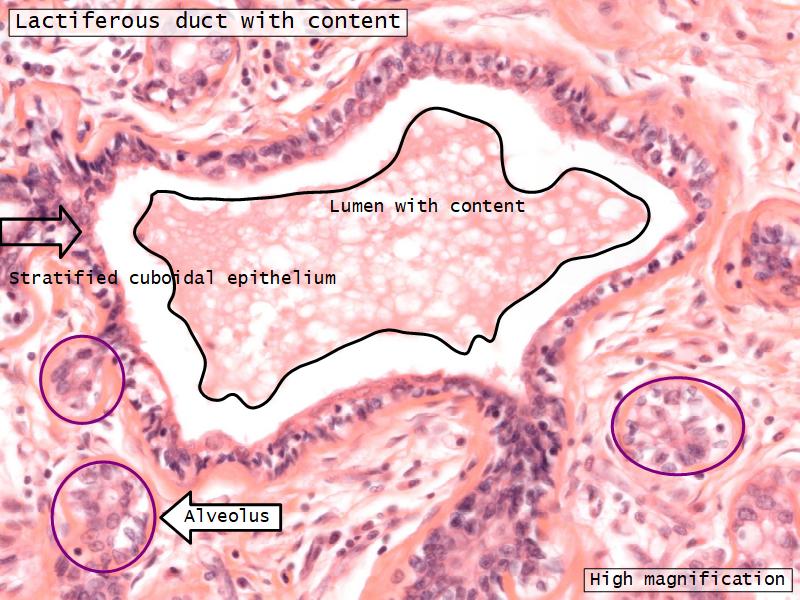

Structures

- Lactiferous sinuses

- Stratified squamous near opening on skin

- Stratified cuboidal other parts

- Lactiferous ducts

- Stratified cuboidal

- Myoepithelial cells

- Underlie lactiferous ducts in most areas

- Basal lamina

- Separate epithelial components from stroma

Active gland

- Much larger than resting phase

- Terminal ducts proliferate to form alveoli

- Alveoli

- Surrounded by incomplete myoepithelial cells